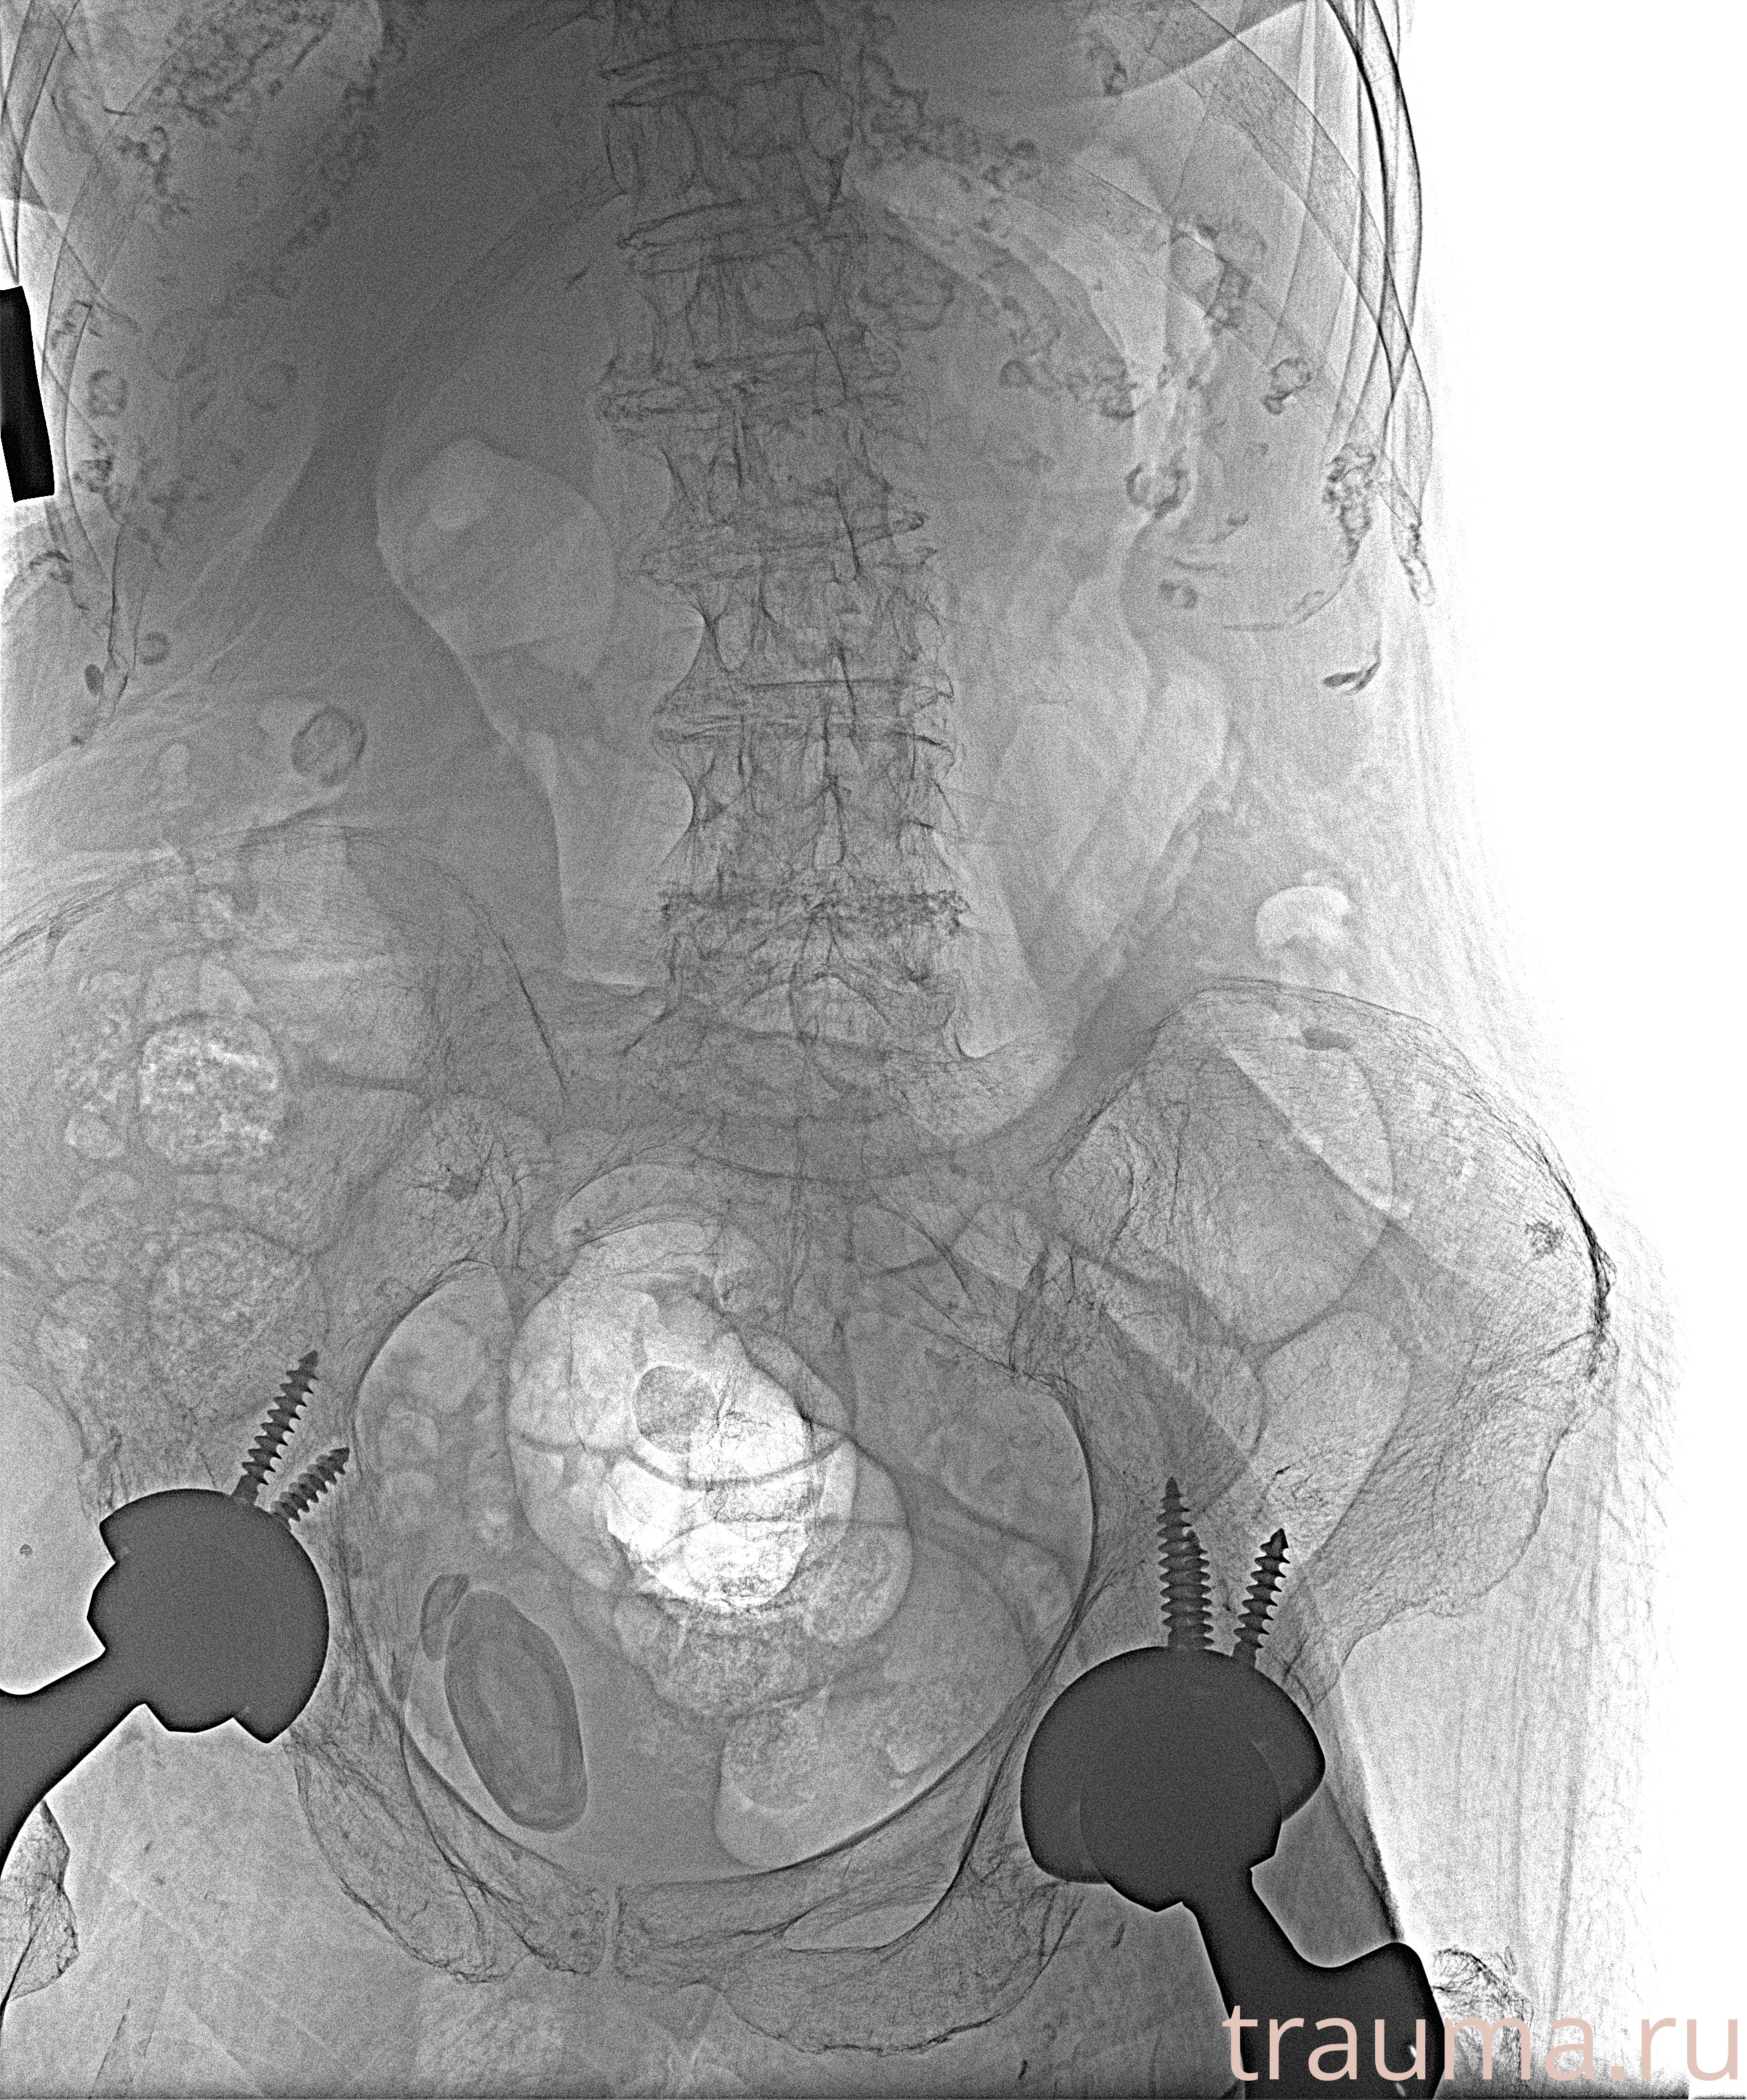

Рентген на дому: по вашему адресу приезжает врач-рентгенолог, травматолог-ортопед с мобильным рентгеновским аппаратом, проводит диагностику травмы или заболевания, делает необходимые рентгенограммы, дает рекомендации по дальнейшему лечению. Получить качественные снимки в домашних условиях возможно благодаря уникальной методике, разработанной МосРентген Центром для института  Склифосовского

при переломе шейки бедра и пневмонии от компании МосРентген Центр - партнера Института имени Склифосовского